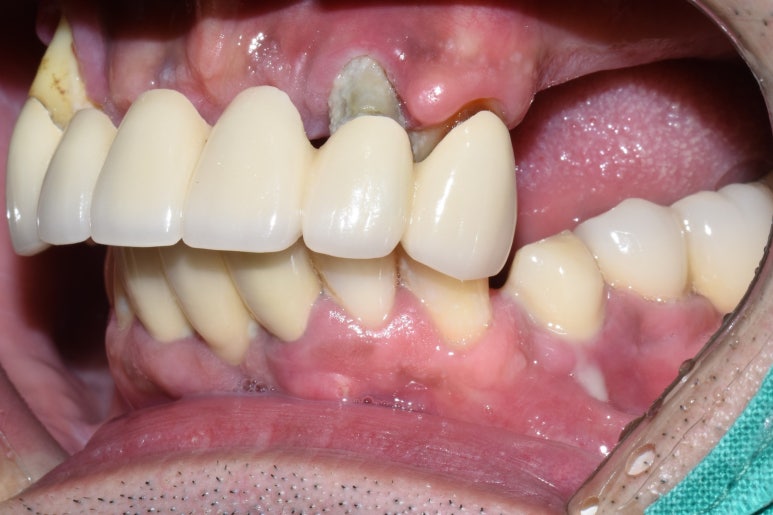

처음 오셨을 때 치아 사진입니다.

앞니가 너무 많이 흔들리고 남은 작은 어금니도 상태가 좋지 않아 다 뽑고 전체틀니를 하기로 했다가

환자분이 아직 50대이시기도 하고 뺐다꼈다 하는 틀니보다는

장기적으로 생각했을 때 임플란트를 하는게 낫다고 판단하신데다가

저희 치과가 서울에서 유명한 임플란트 전문이라고 주변에서 얘기를 들으셨다며

상악 전체임플란트를 하기로 하셨습니다.